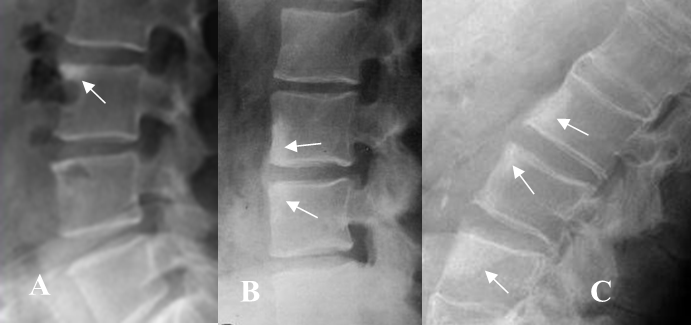

Fig 59 A. Lesiones Romanus.

A, B y C: Rx lateral. Esquinas brillantes en diferentes estados de evolución, por esclerosis de lesiones Romanus, en los cuerpos vertebrales.